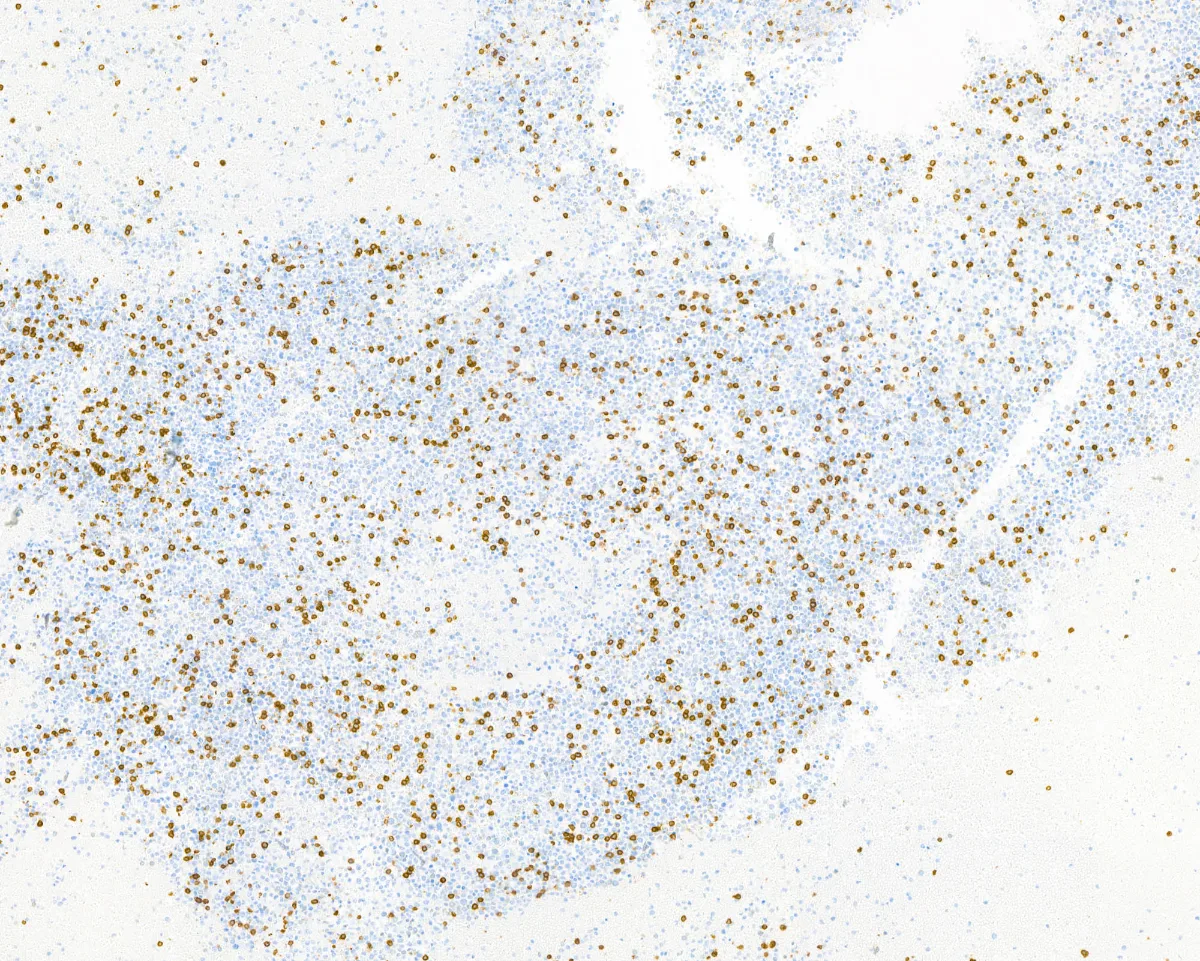

Imágenes:

CD20

- Está compuesto por sábanas de células de tamaño intermedio de origen mieloide, positivas para CD34 y MPO (PMID: 39328673).

- El estudio inmunohistoquímico para detectar marcadores de serie monocítica, tales como CD68, CD163 o MPO puede ayudar a la distinción entre el sarcoma mieloide intracraneal de otros procesos neoplásicos o reactivos (PMID: 40951121).